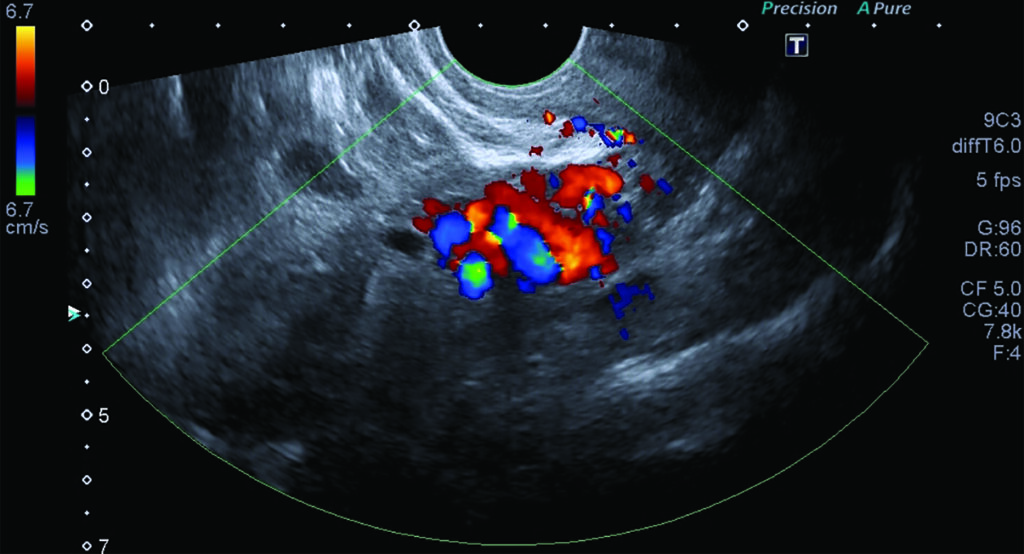

Fig. 7. Doppler color de venas iliacas internas, demostrando flujo reverso del lado izquierdo como signo indirecto de compresión en la VICI.

Se evidencia también flujo reverso en la vena iliaca interna izquierda como signo indirecto de compresión de la VICI (Fig. 7).